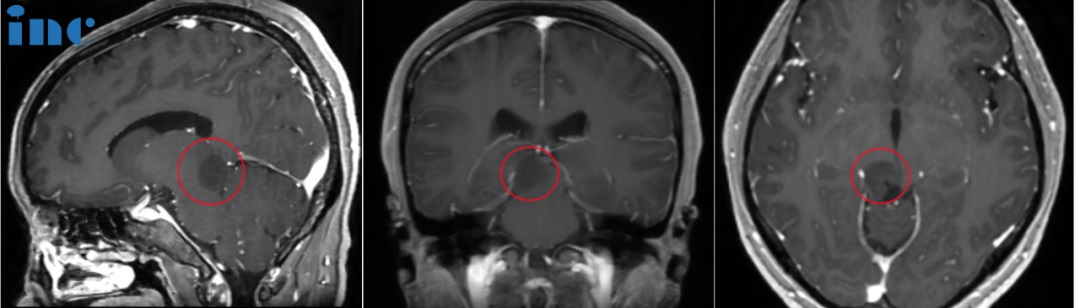

30多岁女性——脑干胶质瘤

“肿瘤还算是早期发现的。如果肿瘤造成了问题,如脑积水或更严重的问题,那很可能已经到了晚期”

30多岁的茵茵2023年10月14日参加单位组织的健康体检时,体检报告出来后发现脑部占位性病变,但患者本身并没有什么明显症状,只不过是之前手偶尔有点麻,很快症状就消失了,因此也没有当回事。后来在当地做了增强核磁后判断有低级别胶质瘤可能,又去做了波普检查,结果是偏恶性肿瘤,医生判断是脑干胶质瘤,级别不算高,医院的建议是做不了手术,只是观察随访。

巴教授表示现在至少有三种观点支持做手术:

一是肿瘤的大小。二是中脑导水管闭塞的风险。三是肿瘤恶性转化的风险。仅凭这三个原因就足以进行手术。

我们遇到有些病人来就诊时已是晚期。他们已经有了症状以及各种问题;可能是因为脑积水而有了分流管,可能肿瘤已经变得大等等。他们总是说,你为什么没有早点来?而茵茵现在的情况是,肿瘤还算是早期发现的。如果肿瘤造成了问题,如脑积水或更严重的问题,那很可能已经到了晚期,那么很遗憾,因为她就已经错过了好时机。

另外,对于手术切除率、手术风险、国内和国外手术是否会有差异等等,巴教授也做了详细评估。